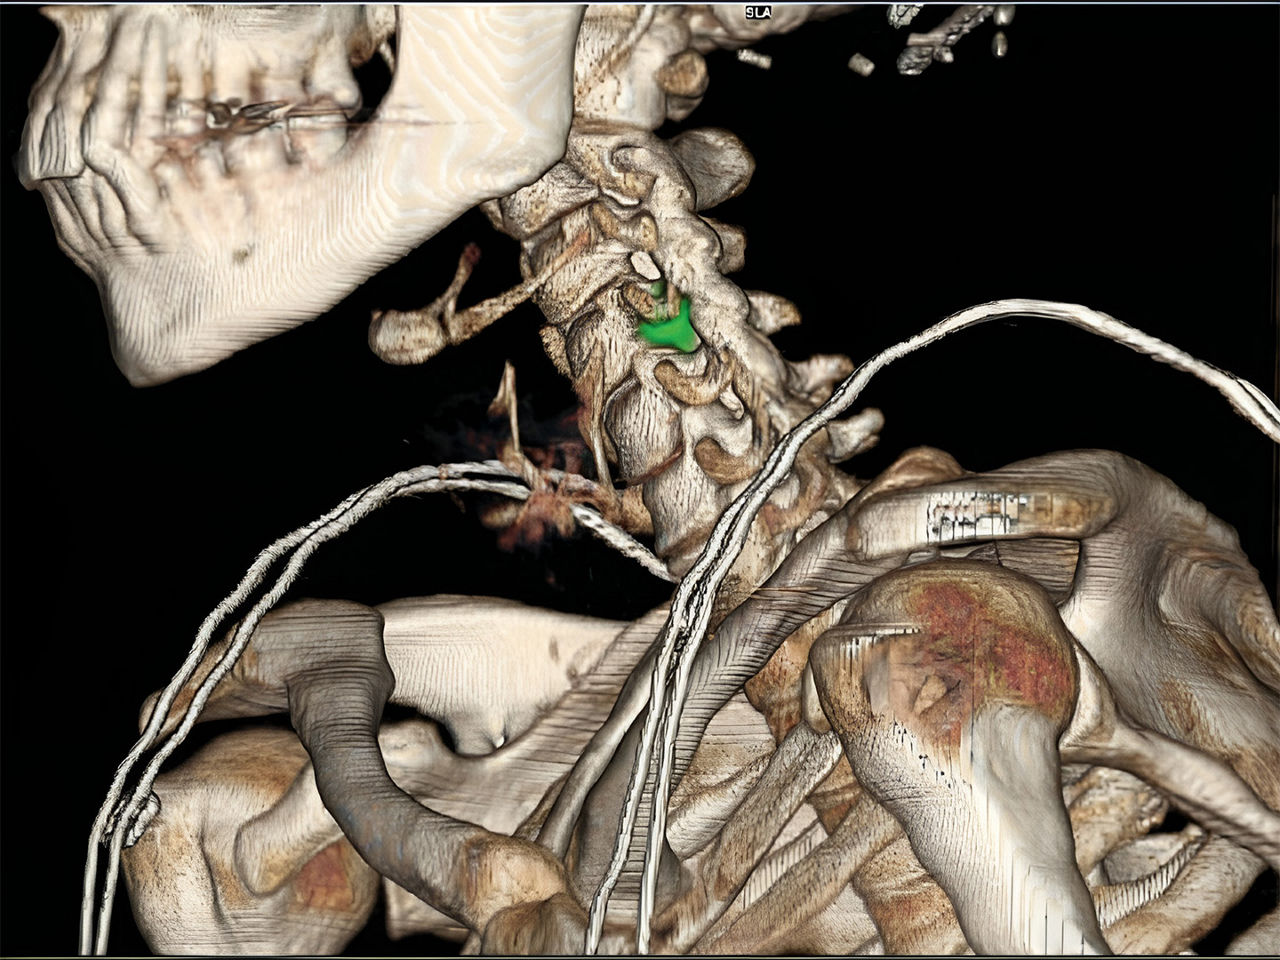

Innovations in SPECT/CT on both the hardware and software side continue to advance the hybrid imaging modality and expand its utility in more clinical areas. For example, StarGuide™ SPECT/CT technology, developed by GE Healthcare, features cadmium zinc telluride (CZT) digital focus detectors, a shape adaptive gantry and an intuitive workflow that automates patient positioning and makes multi-field-of-view quantitative SPECT/CT achievable in routine clinical practice. Hybrid SPECT/CT is currently being used across oncology, cardiology, and neurology. It is used frequently for investigating perfusion and cardiac ischemia, as well as infections, and to image parathyroid disease and thyroid cancer, neuroendocrine neoplasms, bone metastases and prostate cancer.2

An increasing number of clinical applications are finding hybrid SPECT/CT imaging is a useful guide to visualizing disease and treatment progress. When there is a high suspicion of active disease or known structural pathology, for example, SPECT/CT may localize multiple sites and define the extent of disease. In cases where a diagnosis has already been established, SPECT/CT is relied upon for treatment planning, including medical, surgical and radiation therapy planning, as well as monitoring patients’ response to a given treatment. The improved diagnostic accuracy resulting from SPECT/CT is also associated with greater diagnostic confidence and better inter-specialty communication.1 There have also been a growing number of applications for SPECT/CT in cardiac and pulmonary care, such as myocardial perfusion imaging with CT attenuation correction and coronary calcium scoring, and SPECT/CT to evaluate lung perfusion for predicting post-operative forced expiratory volume.

The integration of molecular imaging with radionuclide therapy, also known as theranostics, helps increase opportunities for delivering the right treatment at the right time to each patient and helps pave the way towards highly sensitive radionuclide-based precision medicine. The StarGuide™ SPECT/CT system is also capable of scanning in simultaneous dual-isotope mode, so clinicians can visualize multiple tracers with no temporal variation due to the excellent energy resolution of the CZT detector technology. The ability of CZT to improve spatial and energy resolution contribute to the quantitative accuracy of the imaging modality, which together with the incorporation of sophisticated reconstruction algorithms and AI-based processing, is likely influencing the market growth in its adoption.